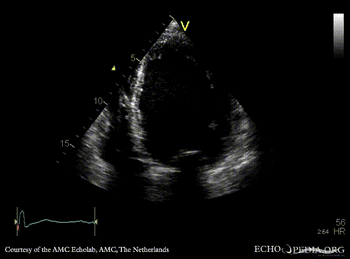

| Courtesy of: AMC Echolab, AMC, The Netherlands | |

| PLAX: Dilated left ventricle with poor function | A4CH |